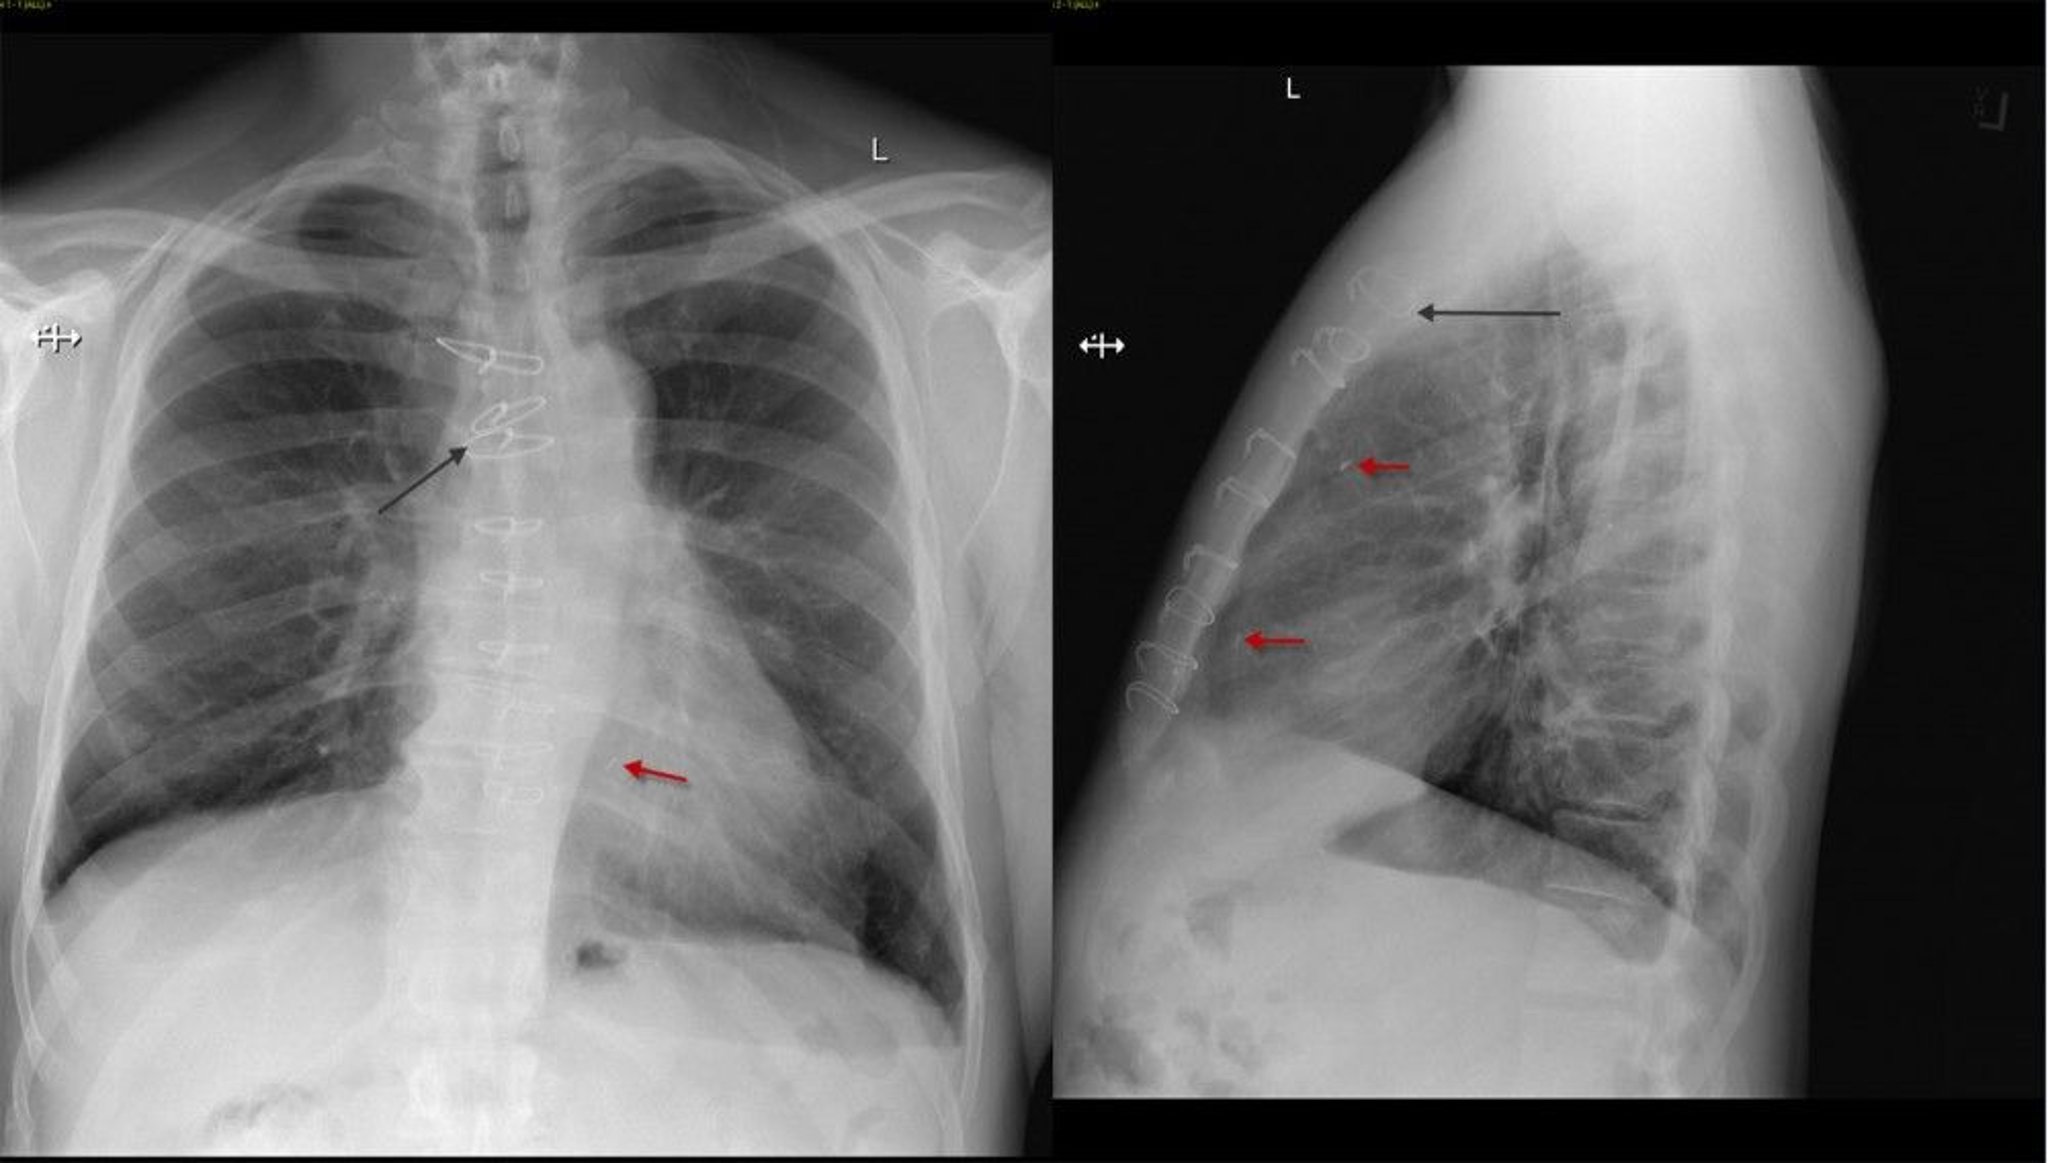

Radiografia frontale e laterale del torace di un paziente dopo intervento di bypass aorto-coronarico che mostra suture sternali (freccia nera) e clip chirurgici (freccia rossa).